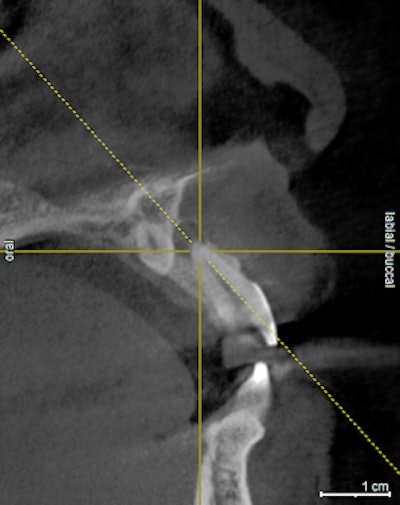

On review of his 3D images, it became apparent that neglecting to intervene earlier had allowed periodontal hard-tissue breakdown to progress to an unmanageable state for tooth #3 and possibly for tooth #14. Tooth #19 was deemed hopeless and could be extracted, bone grafted, implanted, and restored, as the bone volume could be regenerated to receive an implant.

The incidental findings in this scan were multiple: the total resorption of palatal bone in the area of tooth #14 with periapical pathology, and the complete destruction of alveolar support for tooth #3, which was close to undermining the apices of the adjacent premolar #4. The treatment plan was formulated based the images shown.